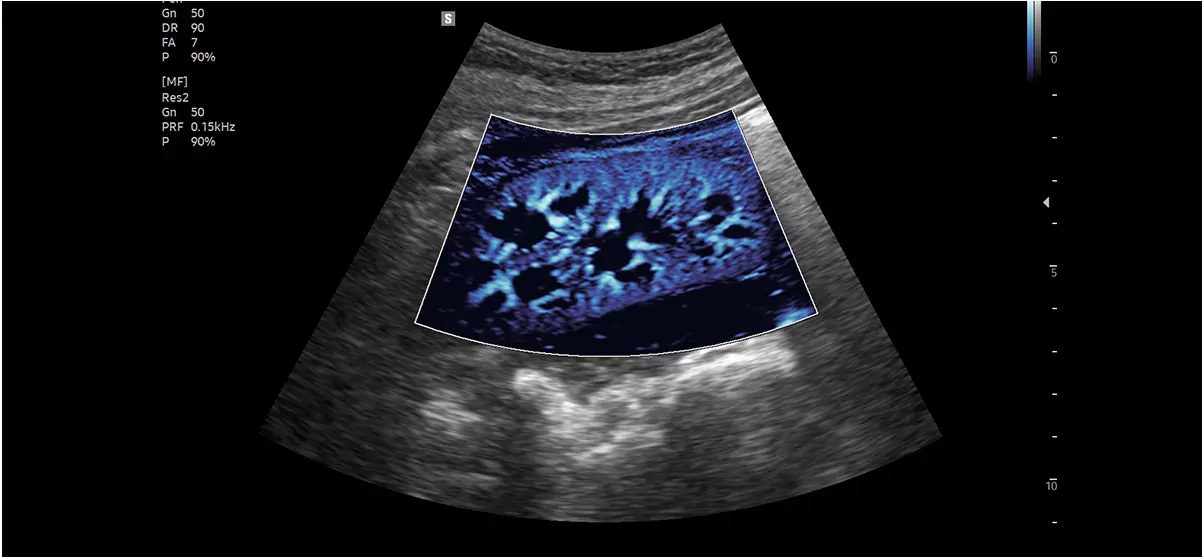

MV-Flow™ візуалізує мікроциркуляторний і повільний кровотік для кольорового відображення інтенсивності кровотоку. Придатний для спостереження мікроциркуляторного кровотоку та об’єму повільного кровотоку.

Нирка з MV-Flow™